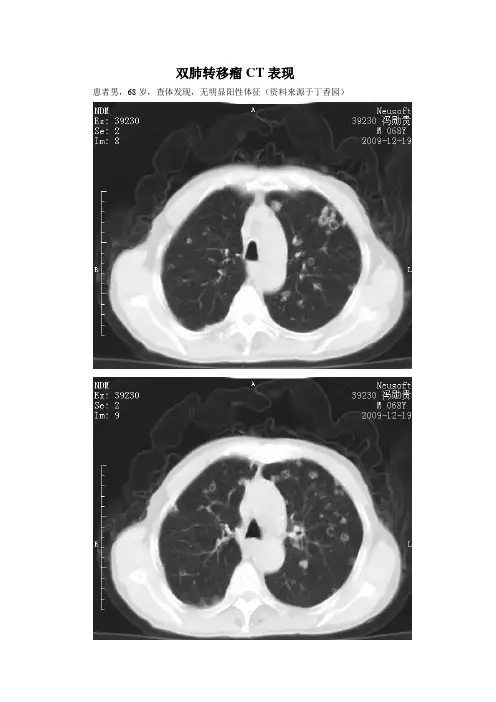

双肺转移瘤CT表现患者男,68岁,查体发现,无明显阳性体征(资料来源于丁香园)分析一:男性,68岁,体健发现双肺多发空洞结节影像表现:左肺下叶外基底段结节病灶,边界不规则,内见空洞,与胸膜粘连,边缘可见长毛刺;两肺见多发小结节灶,包括实变结节,空洞结节,"晕征"结节;纵隔内见淋巴结显示诊断:左下肺肺癌伴双肺转移首先考虑如果是转移,该病例转移结节分布相对较均匀,这点在转移中不常见;看来是急性转移转移结节分布特点:胸膜下;两下肺为主征象分析:空洞型转移---结节4%的肺部转移性结节,发生空洞,多来源于颈部肿瘤及泌尿生殖系统鳞状细胞癌转移结节伴晕征---多来自富血供肿瘤,如血管肉瘤,周围是出血;少数是周围肺泡或肺间质的侵犯引起其他可能:结核;真菌感染;分析二:双肺弥漫大小不等结节状密影,大部分可见囊变,以双下肺及中外带病灶较密集,双肺多发转移的诊断应该没问题,但是在原发灶方面还有要思考的地方。